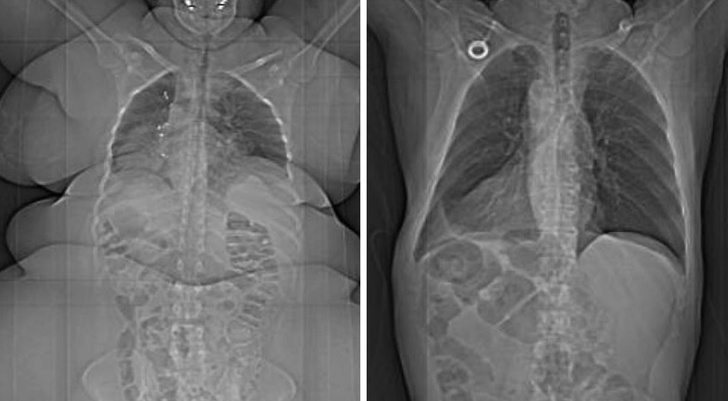

8. Overweight vs healthy weight

Illustration de l'article : 15 fascinating photos that say a lot about the human body

© Unknown / Reddit

12. The body's circulatory system

© Jan Kriwol photography / Facebook © Jan Kriwol photography / Facebook